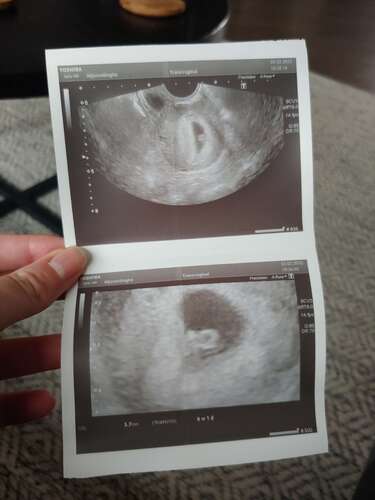

Ik heb een echo gehad met 6 weken en 1 dag. We zagen toen een heel klein vruchtje van ruim 5,5 mm en een kloppend hartje. De gynaecoloog had ons toen al wel gewaarschuwd dat we mogelijk nog geen hartactie zouden zien, dus daar waren we ook van uit gegaan. Dus voor ons was het een meevaller dat we al wel een hartje zagen kloppen. Heel veel succes en hopen op goede echo morgen! Ik weet hoe spannend het kan zijn, zeker na een miskraam/missed abortion